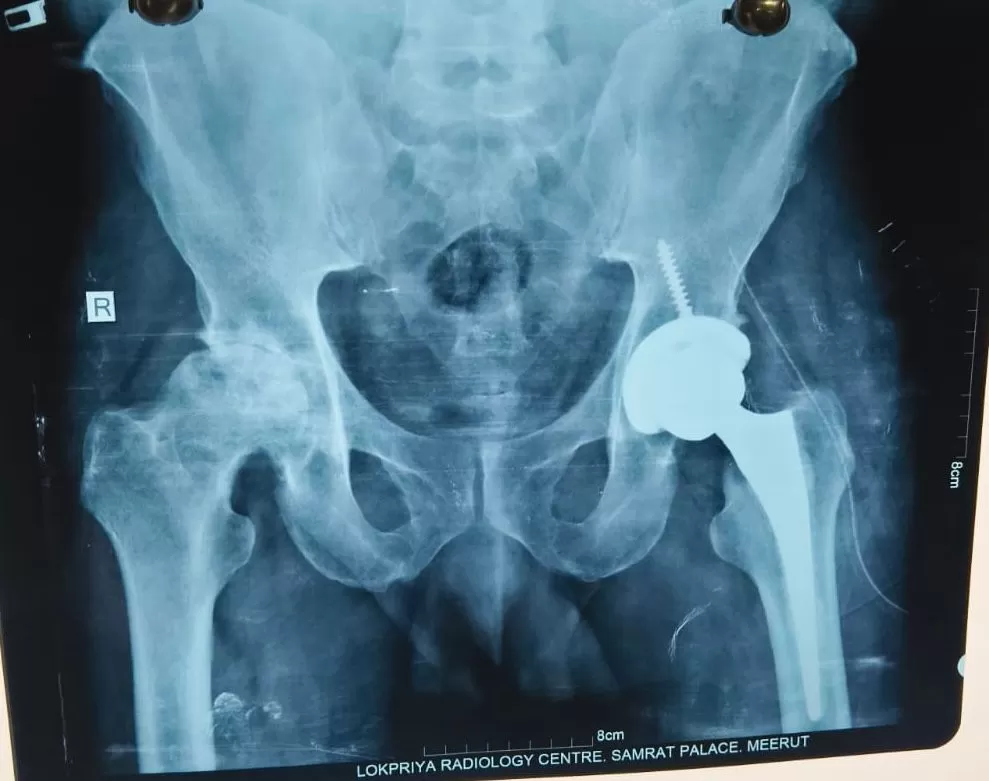

Prempal

Name: Prempal

Date of Operation: 24 March 2026

Age: 30/m Years